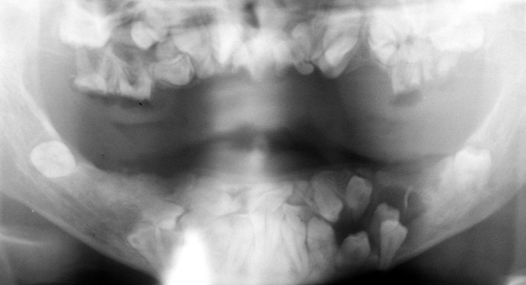

cherubism

cleidocranial dysplasia

pt also has hypoplastic clavicles